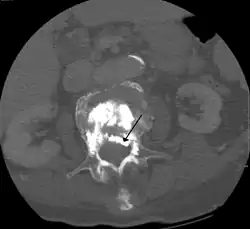

During the procedure, bone cement is injected with a biopsy needle into the collapsed or fractured vertebra. The needle is placed with fluoroscopic x-ray guidance. The cement (most commonly poly methyl methacrylate (PMMA), although more modern cements are used as well) quickly hardens and forms a support structure within the vertebra that provide stabilization and strength. The needle makes a small puncture in the patient's skin that is easily covered with a small bandage after the procedure.[2]